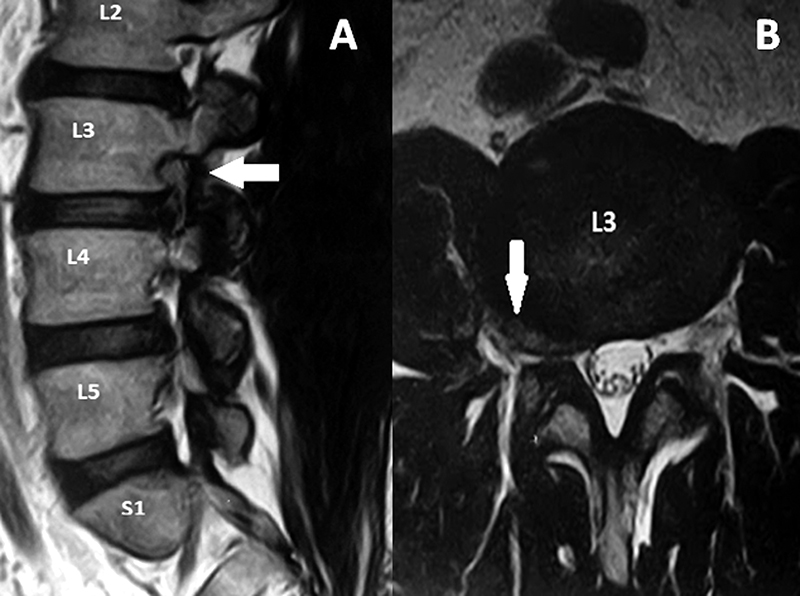

El tubo debe dirigirse al espacio intertransverso del disco a tratar, teniendo como límites del espacio de trabajo, las apófisis transversas a nivel superior e inferior y las apófisis articulares medialmente. Esto se corrobora realizando radioscopia con incidencia anteroposterior y perfil (fig. 1).

Figura 1: Radioscopía intraoperatoria. Colocación del sistema tubular mínimamente invasivo.

Paciente masculino, de 54 años de edad con dolor crural derecha y parestesias en igual región de tres semanas de evolución con escasa respuesta al tratamiento médico. Al examen físico, presentó paresia del cuádriceps derecho e hipoestesia en cara anterior del muslo y dolor según EVA=9. En RM se observa protrusión discal extraforaminal derecha en nivel L3-L4 (fig. 2). Se propuso una discectomía mínimamente invasiva mediante sistema tubular y microscopio. Se observó una mejoría en 8 puntos en la EVA (Video 1).